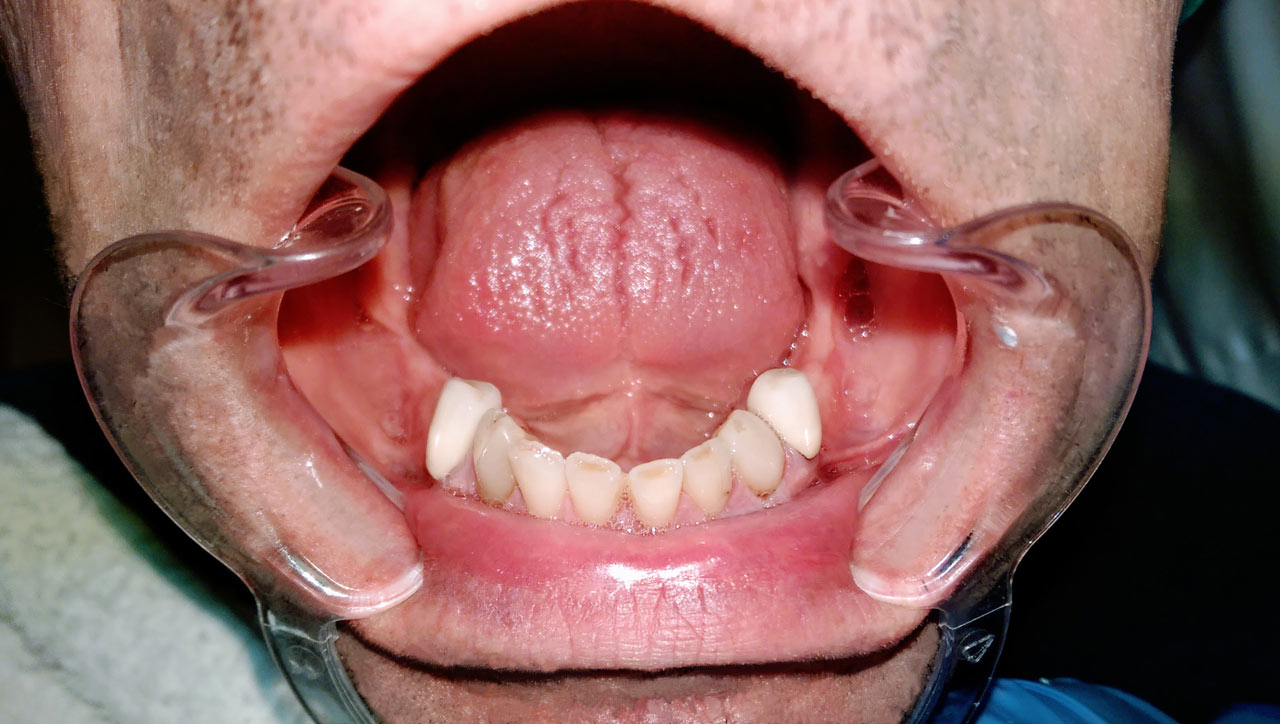

Alsó állcsont teljes rehabilitációja 72 óra alatt

Alsó állcsont teljes rehabilitációja 72 óra alatt, azonnal terhelhető implantátumokkal súlyos paradontitisben szenvedő dohányzó páciens esetében. Az alsó állcsont fogai mind mozogtak az előrehaladott fogágypusztulás miatt.

A fogakat eltávolítottuk, a gyulladt, fertőzött csontot kitakarítottuk, kifertőtlenítettük, majd azonnal implantáltunk.

Svájci, IHDE márkájú, azonnal terhelhető implantátumokat helyzetünk be, és ezekre harmadnapra rögzített, hosszútávú, fémvázas, esztétikus műanyaggal leplezett hidat ragasztottunk be.

Ezt az ideiglenes hidat a sebek gyógyulása miatt használjuk, de tartóssága miatt véglegesként is használható. A legtöbb esetben, ahogy itt is, 6 hónap múlva porcelán hídra cseréljük, a teljes gyógyulás után.